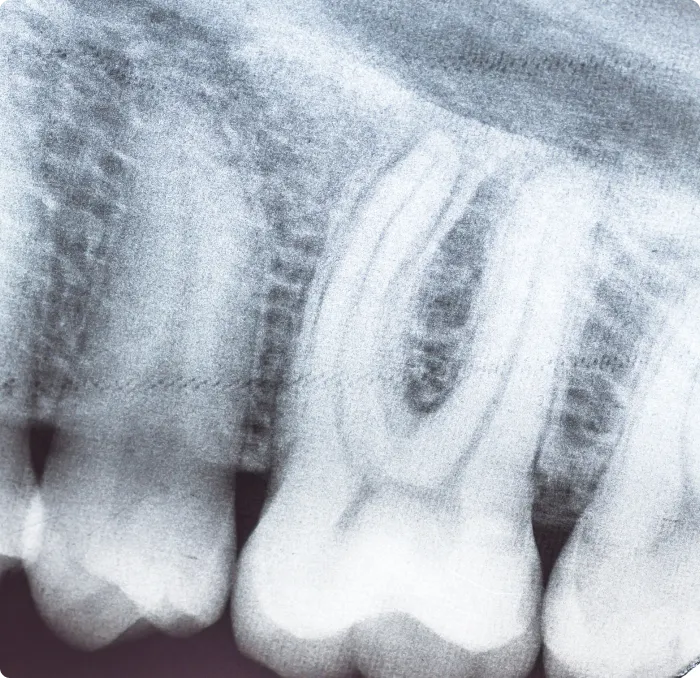

Digital X-rays are a modern diagnostic tool that allows Dr. Kellie Harris and Dr. Kayci Harris to provide precise, safe and efficient care. These images give a detailed view of your teeth, tooth roots and jawbone structure, helping identify oral health concerns that are not visible during a routine exam. By using a small digital sensor instead of traditional film, digital radiography has become a more comfortable and convenient option for patients of all ages.

Digital X-rays also eliminate the need for chemical film development, making the process more environmentally friendly. Once the image is taken, it appears instantly on a computer screen, allowing our dentists to examine it right away. The clarity and resolution of these images make it easier to detect subtle changes, including early signs of decay, bone loss or infections beneath the surface.

• Evaluating periodontal bone loss

• Locating abscesses, cysts or tumors

• Checking the health of tooth roots and surrounding bone

These images play a key role in planning treatments such as root canal therapy, orthodontics, dental implants and tooth extractions. The ability to zoom, enhance and share digital X-rays also supports collaboration with specialists and ensures that your care is tailored to your needs.